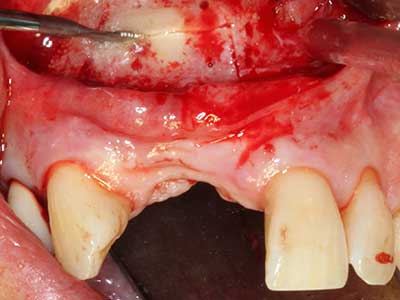

Фиг. 13: Подходяща иригация с остатъчна 4 mm дебелина на костта е важна за този 52-годишен пациент по време на разделянето на костта.

Фиг. 14: Поставяне на RSX имапланта (Bego Implant Systems, Bremen).